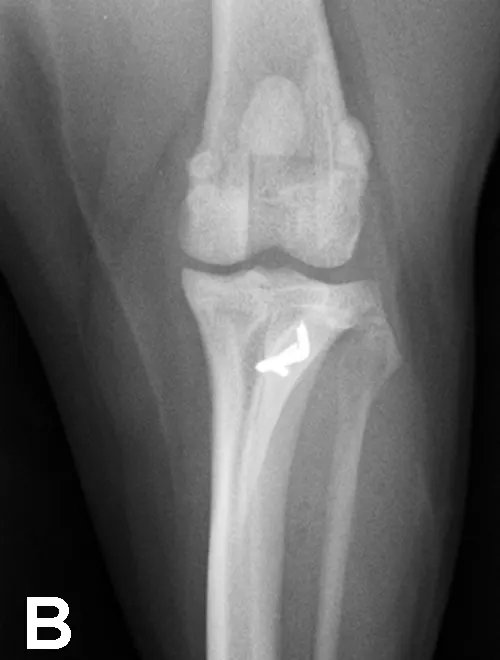

Elbow dysplasia is an umbrella term for several conditions (eg, ununited anconeal process [UAP], medial coronoid disease [MCD], osteochondrosis [OC]/OCD, incongruency) resulting in OA. Most patients are affected by only 1 or 2 of these conditions at the same time (eg, fragmented medial coronoid process, humeral OCD). The causes are multifactorial; genetic and environmental factors are involved. Dogs present with unilateral or bilateral lameness or stiffness of the forelimbs with effusion, pain, and decreased range of motion of the elbow. In dogs older than 5 months of age, radiographs of the joint may show a radiolucent line in the anconeal process (ie, UAP; Figure 3), an articular defect in the medial aspect of the humeral condyle (ie, OC, OCD; Figure 4), sclerosis and blunting of the medial coronoid process (ie, MCD), degenerative changes, or joint incongruency.

MCD (with or without fragment) is the most common among these conditions. Advanced imaging techniques (eg, CT) help in visualization of the coronoid process, which may appear fragmented or sclerotic (Figure 5), be associated with osteophytosis, or have radial incisure irregularities.